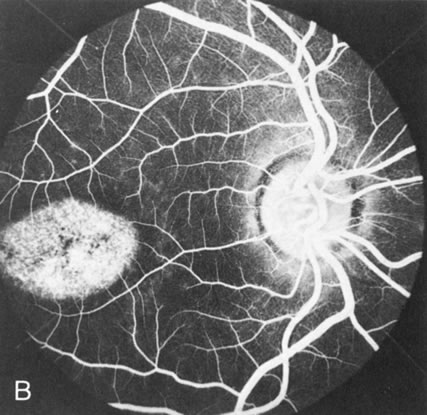

FA plays an important role in the understanding of this rare disorder. In the earliest manifestations of the disease, FA shows a single, isolated choroidal neovascular membrane unassociated with other causes of a membrane, such as drusen or angioid streaks (Fig. 13).25 Presumably this membrane is the cause of the subsequent hemorrhagic maculopathy with secondary disciform scarring, occurring initially in the macula but often extending throughout the retina.

Fig. 13. Hereditary hemorrhagic macular dystrophy (pseudoinflammatory macular dystrophy of Sorsby). Fluorescein angiography in this family member demonstrates that the earliest finding is an isolated choroidal neovascular membrane B). Despite laser photocoagulation, a hemorrhagic maculopathy developed in this eye (C, D) and eventually a disciform scar (E) formed, as it had in the fellow eye, and in the eyes of other affected family members.

Abnormal choroidal perfusion, manifested on FA as a delay in choriocapillaris filling, has been seen in the restudy of some of Sorsby's initial pedigrees.26 This unusual pattern has been related to the histopathologic finding of a “confluent, lipid-containing, amorphous deposit found between the basement membrane of the RPE and the inner collagenous layer of Bruch's membrane.”27